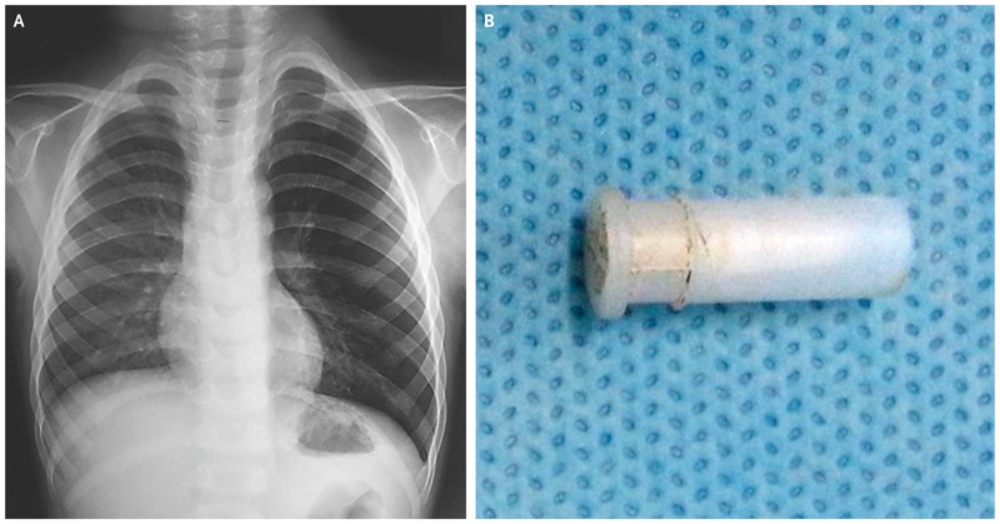

Read moreEl médico al revisar al niño descubrió el motivo que producía ese sonido extraño: se había tragado un silbato. Según ...